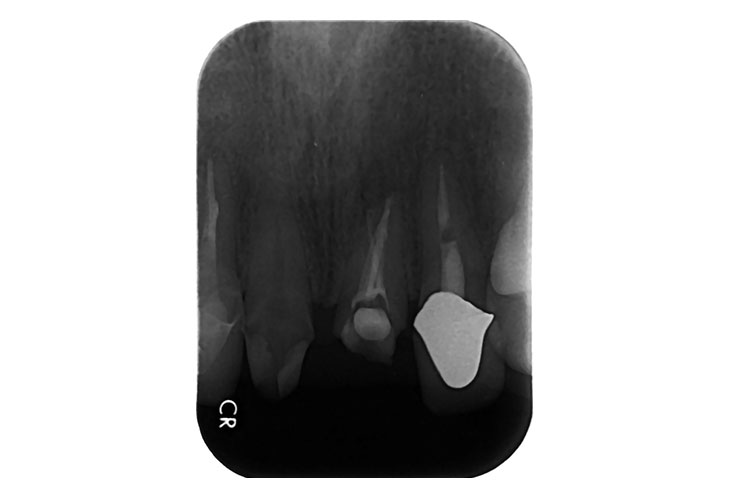

左上1番 抜歯即時インプラント(ルートメンブレンテクニック併用)

BEFORE

AFTER

ルートメンブレンテクニックの併用により、唇側歯肉の豊隆が保持されます。

| 金額 | ¥590,000(税抜) |

| 期間 | 約6ヶ月 |

| リスク | オペから6週までは過大な力がかかると骨の2次安定が得られないことがあるため、注意を要する。 |